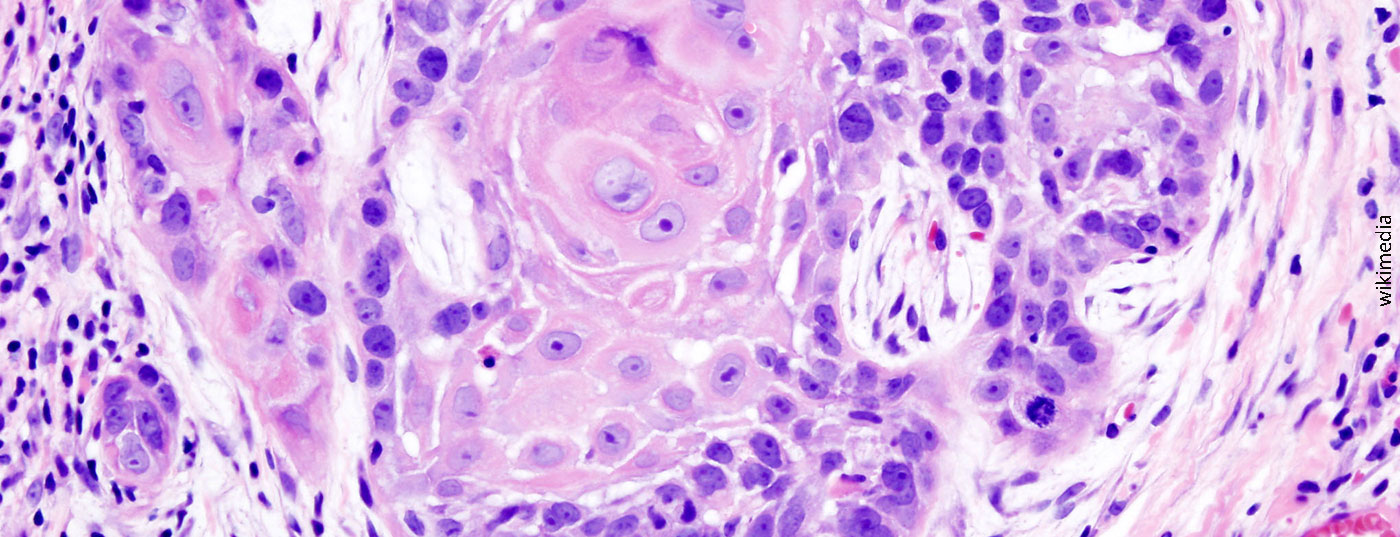

oral_cancer_1_squamous_cell_carcinoma_histopathology

• Plattenepithelkarzinom

Pembrolizumab als Firstline-Therapie senkt Mortalitätsrate

In einer Phase-III-Studie verbesserte Pembrolizumab das Gesamtüberleben bei Patienten mit rezidivierendem oder metastasierendem Plattenepithelkarzinom der Kopf-Hals-Region.